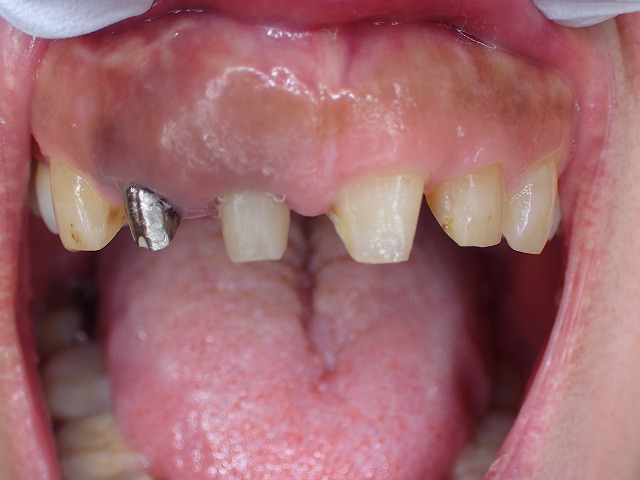

この状態でファイバーコアを制作します。

ファイバー子を装着

メタルボンドを除去した隣の歯は

メタルコアをそのまま利用します。